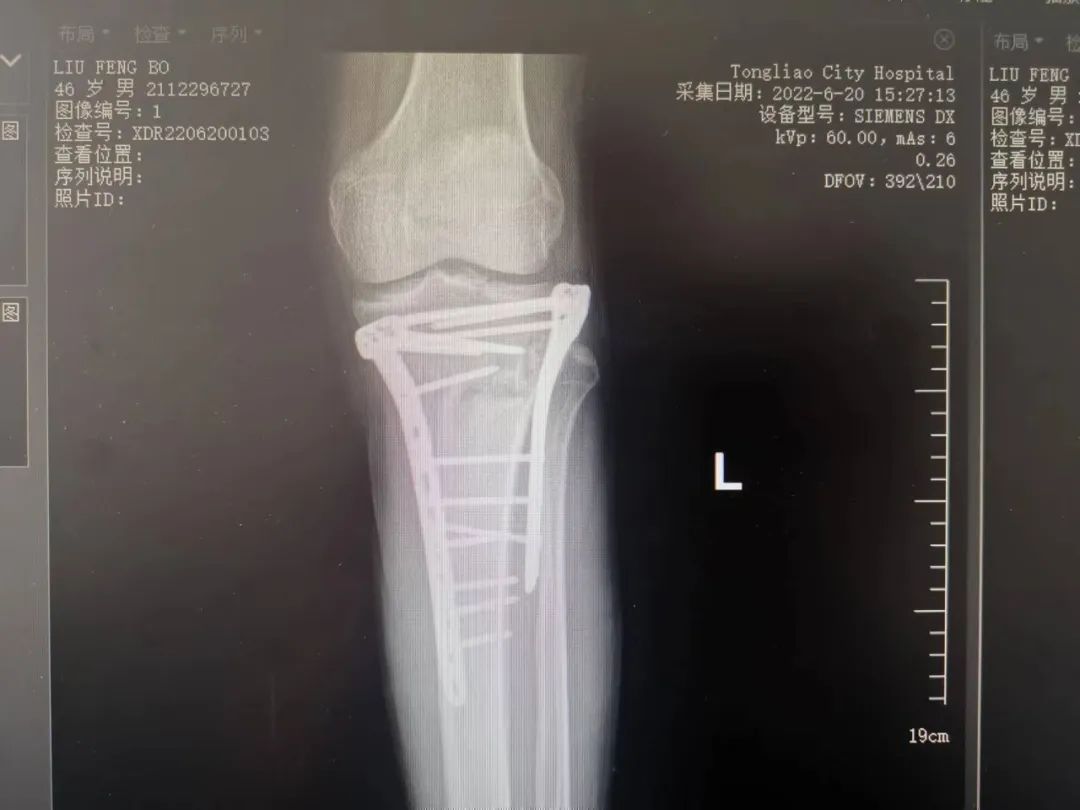

目前,复杂髋臼骨折的治疗仍然是骨科医生面临的最具挑战性的任务之一,随着创伤骨科的迅速发展,人们对创伤控制,加速康复理念的认知不断加深。近日,我院骨一科收治一名因高能量伤致左侧髋臼骨折,左侧胫骨平台骨折患者,其中髋臼骨折分型为:横行伴后壁骨折;胫骨平台骨折分型为Schatzker VI,二者均为该类骨折中最为严重类型,可见其损伤能量极高,如得不到合适的治疗,势必对预后造成致残后果。我院骨一科团队在刘利主任的主持下进行了该患者的术前讨论计划,为其实施了一期左胫骨平台骨折切开复位内固定手术。患者得到左下肢的初始固定后,准备开始着手行复杂髋臼骨折的手术。

张洪彬医生对患者骨盆三维CT进行了术前虚拟仿真,辅助术者规划骨折复位过程及通道螺钉的置入长度、角度及方向。在患者伤后2周内,由刘利主任主刀,采取单一Kocher-Langenbeck 入路手术入路,术中仔细对坐骨神经及旋股内侧动脉进行了保护,降低了远期发生神经损伤及股骨头缺血性坏死发生风险,完成复位后,应用两块重建钢板及一枚通道螺钉就完成了复杂骨折的固定。术后复查DR及CT骨折复位理想,内固定位置满意,没有发生螺钉进入关节腔的情况。患者得到了早期功能康复锻炼的有利条件。患者现已顺利出院。